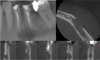

During the pre-operative consultation, the panoramic radiography (Fig. 1) revealed an unilocular radiolucent lesion with a major axis of more than 5 mm, located around the roots of teeth 20 and 21, extending toward the inferior alveolar nerve canal. Cone Beam Computed Tomography (CBCT) imaging showed a radiolucent and homogenous oval lesion with regular contours, measuring 10 × 12.7 × 7.5 mm, erasing the mental foramen and the cortical wall (Fig. 3).

Fig. 3 CBCT sections showing clear cortical vestibular lysis; the letters F, L, and B indicate the Frontal, Lingual, and Buccal planes respectively. |